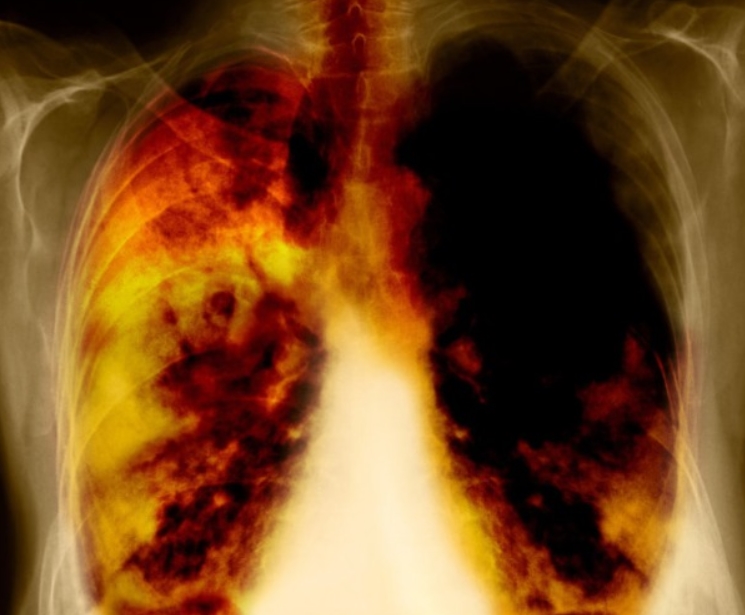

폐CT를 찍으면 생각보다 다양한 걸 알 수 있습니다. 가장 대표적인 건 폐암 조기 발견입니다. 폐암은 초기엔 증상이 거의 없고, 기침이나 흉통이 생길 때는 이미 진행된 경우가 많습니다. CT는 엑스레이로 놓치기 쉬운 2~3mm 크기의 미세한 결절도 잡아냅니다. 실제로 제 지인 한 분은 건강검진에서 폐CT로 아주 작은 결절이 발견돼 조직검사 후 조기에 제거했어요. 또 폐결절, 폐렴, 결핵, 폐기종, 기관지확장증 같은 만성질환도 진단할 수 있습니다. 담배를 오래 피우신 분이나 미세먼지 노출이 많은 분들은 폐기포나 흉막비후(폐를 싸고 있는 막이 두꺼워지는 현상)가 발견되기도 합니다. 예전엔 기침으로 넘기던 증상들이 CT에서는 질환의 초기 신호로 보이기도 하죠. 이렇듯 폐CT는 ‘암만 보는 검사’가 아니라, 폐의 건강 전반을 점검하는 지도 같은 역할을 합니다.

요즘 가장 많이 이용되는 방식이 바로 저선량 폐CT입니다. 말 그대로 방사선 노출량을 낮춘 검사로, 기존 CT 대비 약 70% 정도 방사선이 줄어듭니다. 일반 CT가 약 7mSv라면 저선량 CT는 1~2mSv 수준으로, 1년 동안 자연에서 받는 방사선량과 비슷합니다. 흡연력이 있거나 가족 중 폐암 이력이 있는 분들에게 국가에서 권장하는 검진 항목이기도 합니다.

CT라 하면 가장 걱정되는 게 방사선 노출입니다. 하지만 요즘 장비는 예전보다 훨씬 안전합니다. 자동 노출조절 기능과 인공지능 재구성 기술 덕분에 방사선량이 10년 전보다 절반 이상 줄었어요. 저선량 CT는 일반 CT보다 노출이 훨씬 적고, 한 번 촬영으로 암이 생길 확률은 거의 없습니다. 오히려 조기에 질병을 발견해 치료하는 이점이 훨씬 큽니다.

| 1 | 폐암 | 폐CT로 가장 중점적으로 확인하는 질환입니다. 작은 결절(혹) 단계에서 조기 발견이 가능하며, 폐엽 내부 깊숙한 부위까지 세밀하게 확인할 수 있습니다. |

| 3 | 폐렴 | 세균이나 바이러스 감염으로 생긴 염증을 구체적으로 확인할 수 있으며, 엑스레이보다 염증 범위와 진행 정도를 명확히 구분합니다. |

| 5 | 폐기종 | 흡연으로 폐포가 파괴되어 공기 주머니가 비정상적으로 커진 상태로, 폐CT에서 기포 모양(벌집 모양)이 뚜렷이 보입니다. |